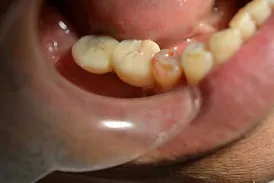

A Customised Dental Crown Is Then Placed On The Implant To Provide The Finishing Touch. Our clinic utilises the latest technologies and dental expertise to make sure that the dental implant feels, looks and functions like a natural tooth. In fact, it may be difficult to distinguish between the dental implant itself and your real teeth.

Dental implants are a game-changer for those dealing with tooth loss. They offer many benefits that traditional tooth-replacement options cannot provide. Some of the benefits include